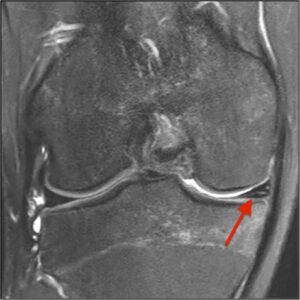

Resonancia magnética

Si se sospecha una lesión meniscal aguda, y fuera del cuadro de un bloqueo agudo de la rodilla, se debe realizar un estudio por resonancia magnética (RM) para precisar el tipo de lesión y el estado del LCA y buscar posibles contusiones óseas